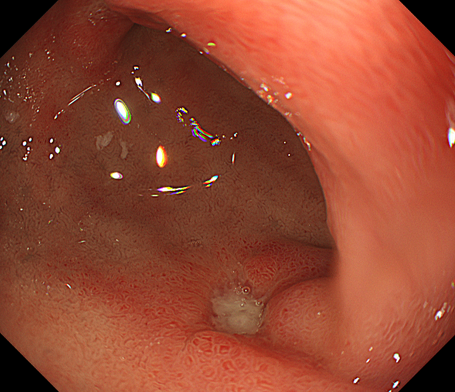

十二指腸潰瘍とは、十二指腸の粘膜に炎症が起きて、深い傷(潰瘍)ができている状態を指します。

特に十二指腸の中でも、最も胃に近い球部で起こりやすいと言われています。

• 内視鏡検査